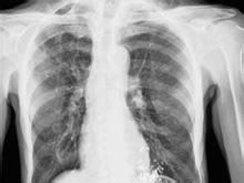

椎管内结核肉芽肿又叫椎管内结核瘤,椎管内结核瘤是继发于身体其他部位的结核病变,结核菌绝大多数是由身体其他部位的结核病灶经血行播散到椎管内,

结核性脑膜炎的病变也可以直接播散侵犯脊髓。椎管内结核肉芽肿是由原发病灶的结核病转移病转移,或结核菌经血行或淋巴侵入脊柱的结果,结果是引起脊柱破坏和硬脊膜外冷脓肿结核性肉芽肿。